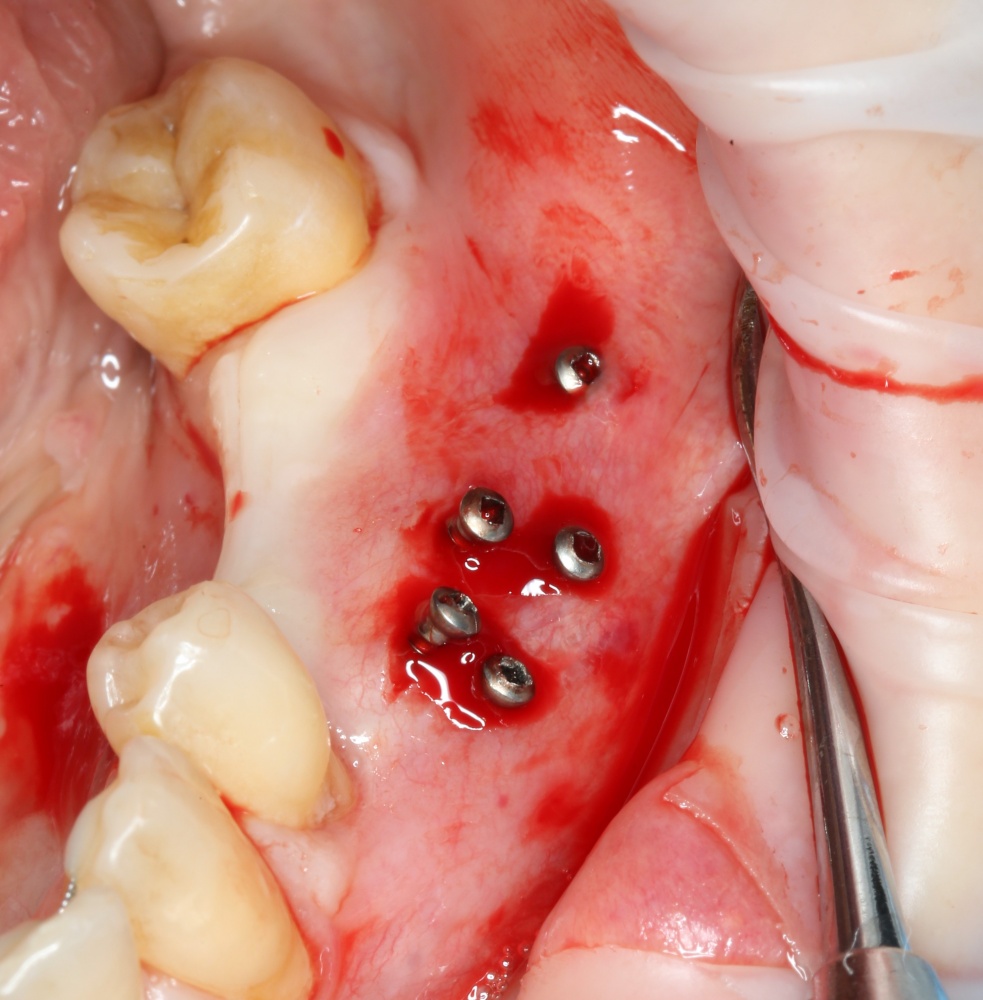

Теперь можно готовить лунки под импланты:

A09A5459 (2)

В данном случае я планирую установить импланты Nobel Replace Conical Connection:

A09A5461 (2) A09A5462 (2)